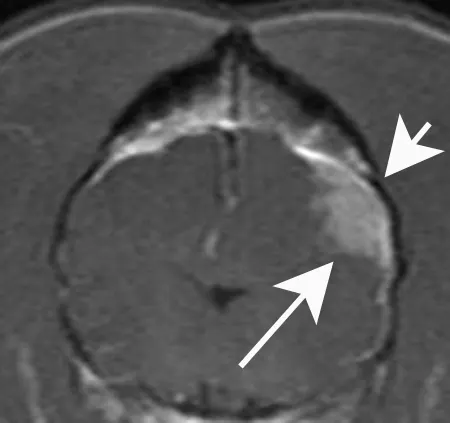

A transverse postcontrast T1- weighted MRI of the brain of a dog with a meningioma that caused seizures. The tumor is clearly evident as a homogeneously enhancing mass (long arrow). Note that the skull directly over the mass is increased in thickness (short arrow), a common finding with meningiomas.